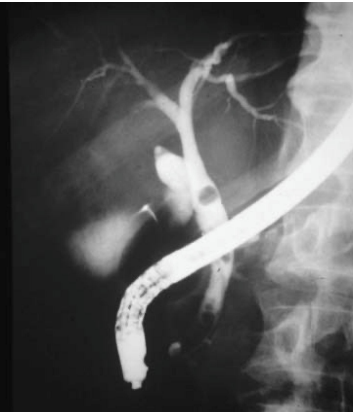

3.2. ERCP

Vừa chẩn đoán và can thiệp, độ nhạy 80-93% và độ đặc hiệu 99-100%. Tuy nhiên là biện pháp xâm lấn, đòi hỏi kỹ thuật, liên quan nhiều biến chứng như viêm tuỵ cấp, chảy máu, thủng tá tràng… Chỉ định khi:

Chụp đường mật trong mổ: Với sỏi đường mật đã xác định, hoặc trong cắt túi mật do sỏi: chụp đường mật trong mổ giúp:

- Đánh giá đặc điểm, số lượng, vị trí và kích thước sỏi;

- Nghiên cứu hình thái cây đường mật;

- Quyết định chiến lược can thiệp.